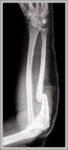

Muscular arteries like femoral or radial distribute blood flow via thick tunica media of smooth muscle regulating resistance through vasoconstriction or dilation, elastic arteries like aorta buffer pulsatile flow with…